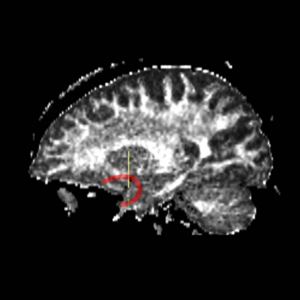

Fornix

ROI 1 was drawn on the sagittal slice, 5 slices superior to the anterior commisure (Fig. 8 & 10). ROI 2 was drawn on a coronal slice where the crux of the fornix was present. It was not always the same slice for both sides (Fig. 9 & 11).

Figure 10. Sagittal View of Fornix, ROI 1 (both left and right)

Figure 11. Sagittal View of Fornix, ROI 2 (right)